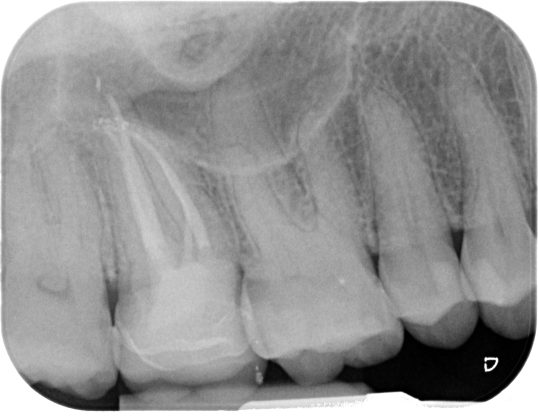

Una cavità d’accesso inadeguata per posizione, profondità ed estensione può determinare serie difficoltà nelle fasi successive, rendendo ad esempio difficile la localizzazione degli orifizi canalari, sottoponendo a eccessivo stress gli strumenti meccanici utilizzati o determinando un indebolimento della struttura dentale residua (Figure 1-5).

Devono essere valutate con molta attenzione la posizione dell’elemento in arcata e la sua inclinazione (Figure 6-7), l’entità e la posizione del processo carioso se presente, gli eventuali restauri posizionati sul dente e i rapporti con il parodonto: tutte queste considerazioni permetteranno al clinico di capire innanzitutto la mantenibilità e la possibilità di isolare mediante diga di gomma il dente. L’interpretazione degli esami radiografici consentirà inoltre di valutare alcuni parametri preoperatori di notevole importanza:

Un’attenta analisi di questi dati clinici e radiografici consentirà al clinico di ridurre notevolmente il rischio di errori grossolani in questa delicata fase del trattamento.